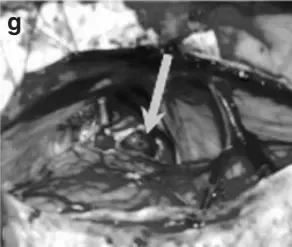

术中情况:通过幕下小脑上入路暴露病变。大脑中心部位血管错综复杂,无论哪根血管都不能伤及。事实上,在手术期间,有很多血管像“门帘”一样遮挡在肿瘤上面,而肿瘤就躲藏在血管门帘的后方。巴教授精湛的技艺巧妙避开重要的血管。

在术中照片(g)上可以看到手术的核心区域,那个让人头疼的海绵状血管瘤已经被术者取出,照片上用箭头指的地方,原本应该是血管瘤的地盘,现在空空如也,连一丝一毫的残留都找不到(箭头)。